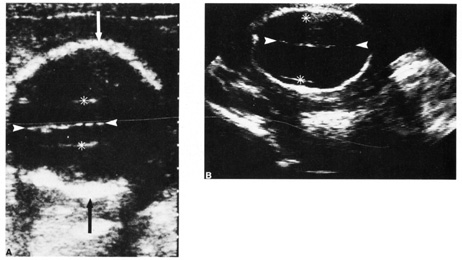

of neurologic deficits (see Fig. 6).  Fig. 6. A: First-trimester twin intrauterine gestations. Ultrasound examination

of the pregnant uterus (arrowheads) shows the “owl eyes” characteristic of early twin pregnancies. B: Maternal urinary bladder. (Courtesy of Alfred B. Kurtz, MD) Fig. 6. A: First-trimester twin intrauterine gestations. Ultrasound examination

of the pregnant uterus (arrowheads) shows the “owl eyes” characteristic of early twin pregnancies. B: Maternal urinary bladder. (Courtesy of Alfred B. Kurtz, MD)

| Fetal number (Fig. 6) |

| | Biophysical profile |  Fig. 11. Early second trimester ultrasound showing posterior neck cystic mass consistent

with cystic hygroma. Image courtesy of GE Medical Systems. Fig. 11. Early second trimester ultrasound showing posterior neck cystic mass consistent

with cystic hygroma. Image courtesy of GE Medical Systems.

|

Fig. 12. Duodenal atresia in a second trimester fetus. A: Ultrasound scan of fetal abdomen (arrowheads) showing two fluid-filled structures (arrows). Increased amniotic fluid (polyhydramnios) surrounds the

fetus. B: Newborn radiograph of upper abdomen demonstrating gas-filled stomach (S) and duodenum (D), which are typical findings of duodenal atresia. (Courtesy

of Alfred B. Kurtz, MD) Fig. 12. Duodenal atresia in a second trimester fetus. A: Ultrasound scan of fetal abdomen (arrowheads) showing two fluid-filled structures (arrows). Increased amniotic fluid (polyhydramnios) surrounds the

fetus. B: Newborn radiograph of upper abdomen demonstrating gas-filled stomach (S) and duodenum (D), which are typical findings of duodenal atresia. (Courtesy

of Alfred B. Kurtz, MD)

|